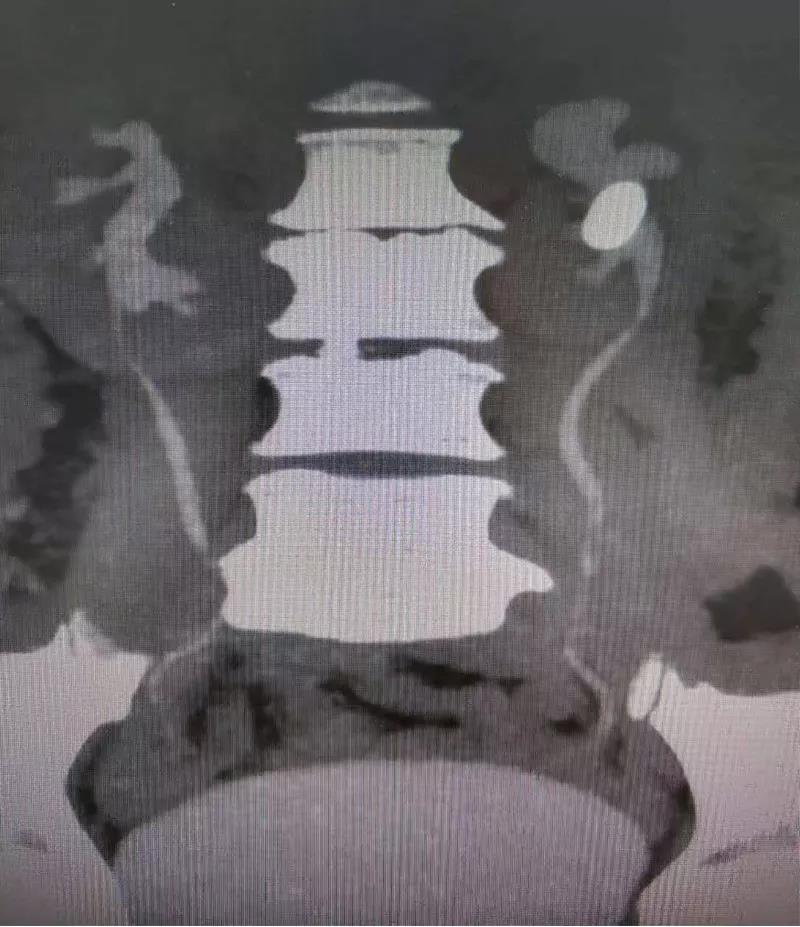

患者,男性,56岁。因左侧腰背部酸胀不适于1月前入院治疗,ctu示:左侧肾脏部分鹿角型结石,大小约31*18mm,左肾积水。于2019年7月26号行左输尿管软镜下取石术。现为进一步治疗左肾结石,收治入院。

2019年6月3日本院CTU:左侧肾盂输尿管交界处结石,左肾积水。双肾多发结石。双肾囊肿。

左肾盂输尿管交界处结石,左肾积水,双肾结石,双肾囊肿,高血压病,冠心病,双侧输尿管结石手术史

CTU:左肾盂输尿管移行段结石,其上尿路中重度积水,双肾旋转不良。